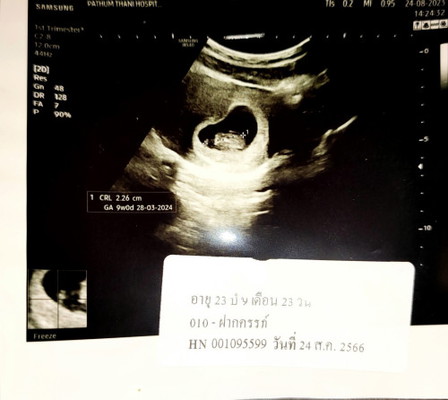

บ้านนี้ไม่แน่ใจเลยว่าท้องจริงหรอท้องลมค่ะ หมอบอกว่าอาจจะเป็นท้องลมค่ะแม่ๆคนไหนดูเป็นบ้างค้ะ

ของเรา 9วีค2วัน แต่หมอบอกไม่เจอตัวเด็ก แต่ภาพที่ได้ ❗❗ เราเลยไม่รู้ว่าเราตาฟาดรึป่าว ท้องแรกค่ะ